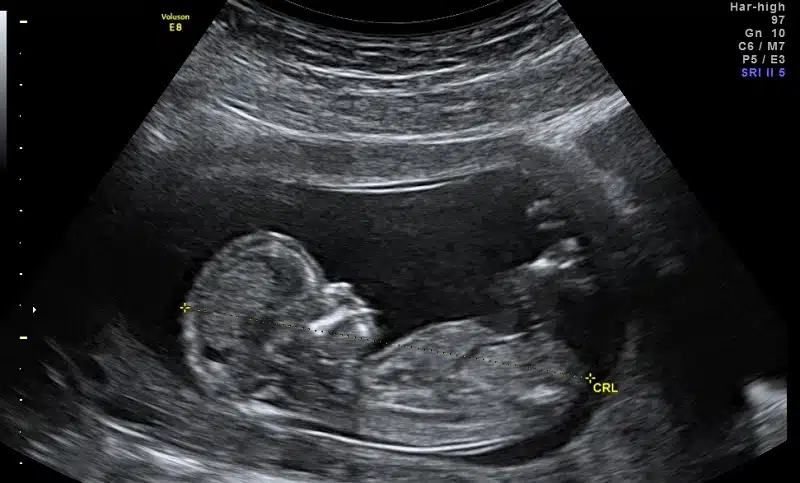

La revue scientifique Nature Communications a récemment publié une étude clinique marocaine sur l’automatisation de la biométrie fœtale et les évaluations du volume de liquide amniotique. Elle vient de valider scientifiquement la solution élaborée par la start-up DeepEcho.

Selon cette étude, la biométrie fœtale et les évaluations du volume de liquide amniotique sont deux tâches essentielles mais répétitives dans les échographies de dépistage fœtale, aidant à la détection d’affections potentiellement mortelles.

Selon la même source, ces deux tâches sont essentielles dans l’écographie fœtale "parce qu’elles permettent de détecter le retard de croissance intra-utérin, première cause de mortalité fœtale dans le monde, et les anomalies liées à la quantité du liquide amniotique, dont nous avons automatisé la quantification", explique-t-il.

L’intérêt de cette étude relève de son caractère prospectif. Ces modèles automatisés ont été formés à l’aide d’une base de données récentes constituées de 172.293 images échographiques fœtales marocaines anonymisées.